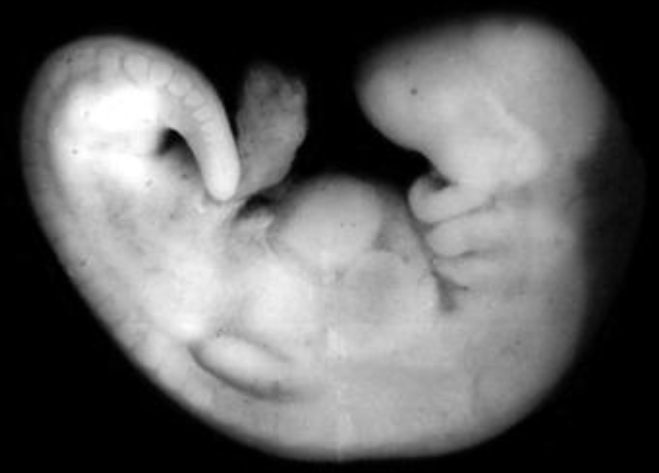

Comment différencier un SC 11 / 12 / 13 sur une photo ??

==> Principalement grâce aux bourgeons des membres:

- Au SC 11 il n'y en a pas

Image

- Au SC 12 il y a le bourgeon des membres supérieurs

- Au SC 13 il y a le bourgeon des membres supérieurs ET inférieurs

Est ce que tu vois la différence à présent ?